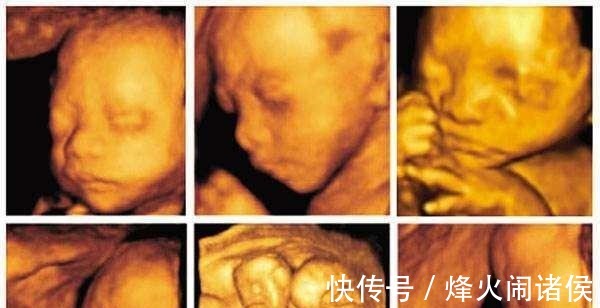

文章插图

2、如何看懂四维彩超单这才是重头戏,对不对啊。下面我们就来分享四维彩超除了排畸外,我们应该看那些重要数据:

胎头:胎头轮廓完整,说明胎儿正常。如果是缺损或者变形就是胎儿有异常。胎头脑中线无移位、没有积水是正常发育。胎头双顶径测量:这个数字是宝宝成熟度的指标。孕26周到36周时每周增加0.2厘米;36周增长速度减半。这个数据还可以预估胎儿体重。胎儿双顶径在8.5cm,体重约为2500g,如果是9.1cm。体重约为3500个左右;当大约10cm,胎儿体重也就超过4000g了。胎心:这个很容易了。胎心强,清晰有力是正常。如果胎心弱,也有可能是宝宝在睡觉,另一种情况就是胎儿胎心发育有问题。正常胎心率在120--160之间。

胎盘:胎盘正常厚度是25--50mm。胎盘成熟度一般为0、Ⅰ、Ⅱ、Ⅲ四级。孕初期多为0级。到了孕中后期,随着胎盘的成熟,开始向Ⅲ级发展。孕37周后多为Ⅲ级。股骨长度:这个数据指的是宝宝大腿骨的长度。一般比胎头双顶径数据小20到30mm。羊水:羊水深度在3-7厘米是正常的羊水深度。超过7厘米羊水过多,少于3厘米过少。过多过少对宝宝发育都是不利的脐带:脐带在羊水中漂浮是正常的,但是出现脐带出现在胎儿颈部,就又脐带绕颈的可能。